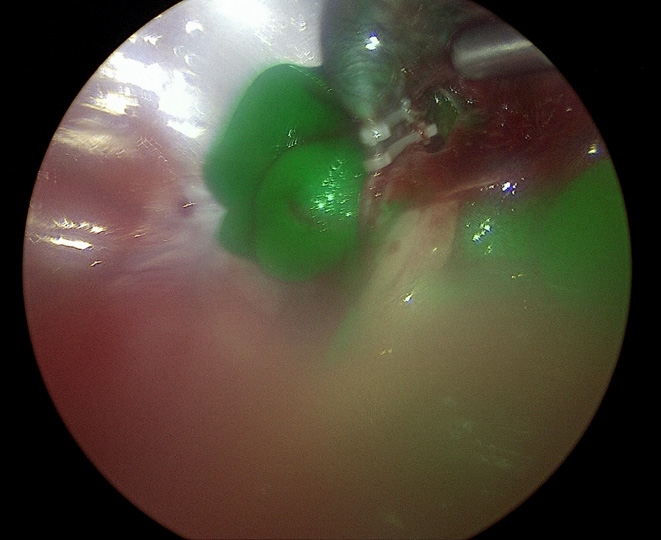

관절경 Arthroscopy 관절

관절경은 작은 절개를 통해 관절 내부에 카메라(관절경)를 삽입하여 병변을 직접 확인하고, 치료하는 최소침습 수술입니다.

주요 적용증은 십자인대 파열, 연골 손상, 관절 내 이물 등 입니다. 정확한 진단과 동시에 치료가 가능해 수술 효과가 높고 회복이 빠르며, 통증과 출혈이 적다는 것이 큰 장점입니다

관절경

관절경 수술 장면 이미지